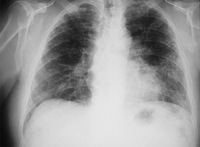

Sarcoidosis: CXR demonstrating bilateral hilar lymphadenopathy plus pulmonary infiltrates

Adapted from BMJ (2009); used with permission